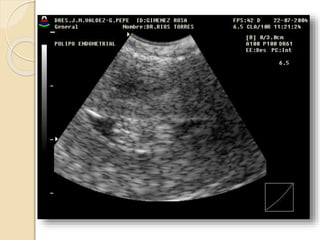

POLIPO ENDOMETRIAL

Se forman por una proliferación

anómala focal o multifocal de la capa

basal del endometrio y del estroma.

Son mas sensibles al estímulo

estrogénico y por esto es frecuente que

coexistan con una hiperplasia

endometrial.

Pueden ser sésiles o pediculados, únicos o múltiples y de

tamaño variable.

Suelen ser hiperecogénicos y en su espesor pueden

apreciarse pequeñas imágenes econegativas quísticas de

diferente tamaño.

Con la ayuda del Doppler color podemos identificar el

pedículo vascular.

La histerosonografía diagnóstica con nitidez la existencia

de pólipos endometriales. Incluidos los de dimensiones

reducidas, su numero, localización, su inserción y las

características del endometrio adyacente.